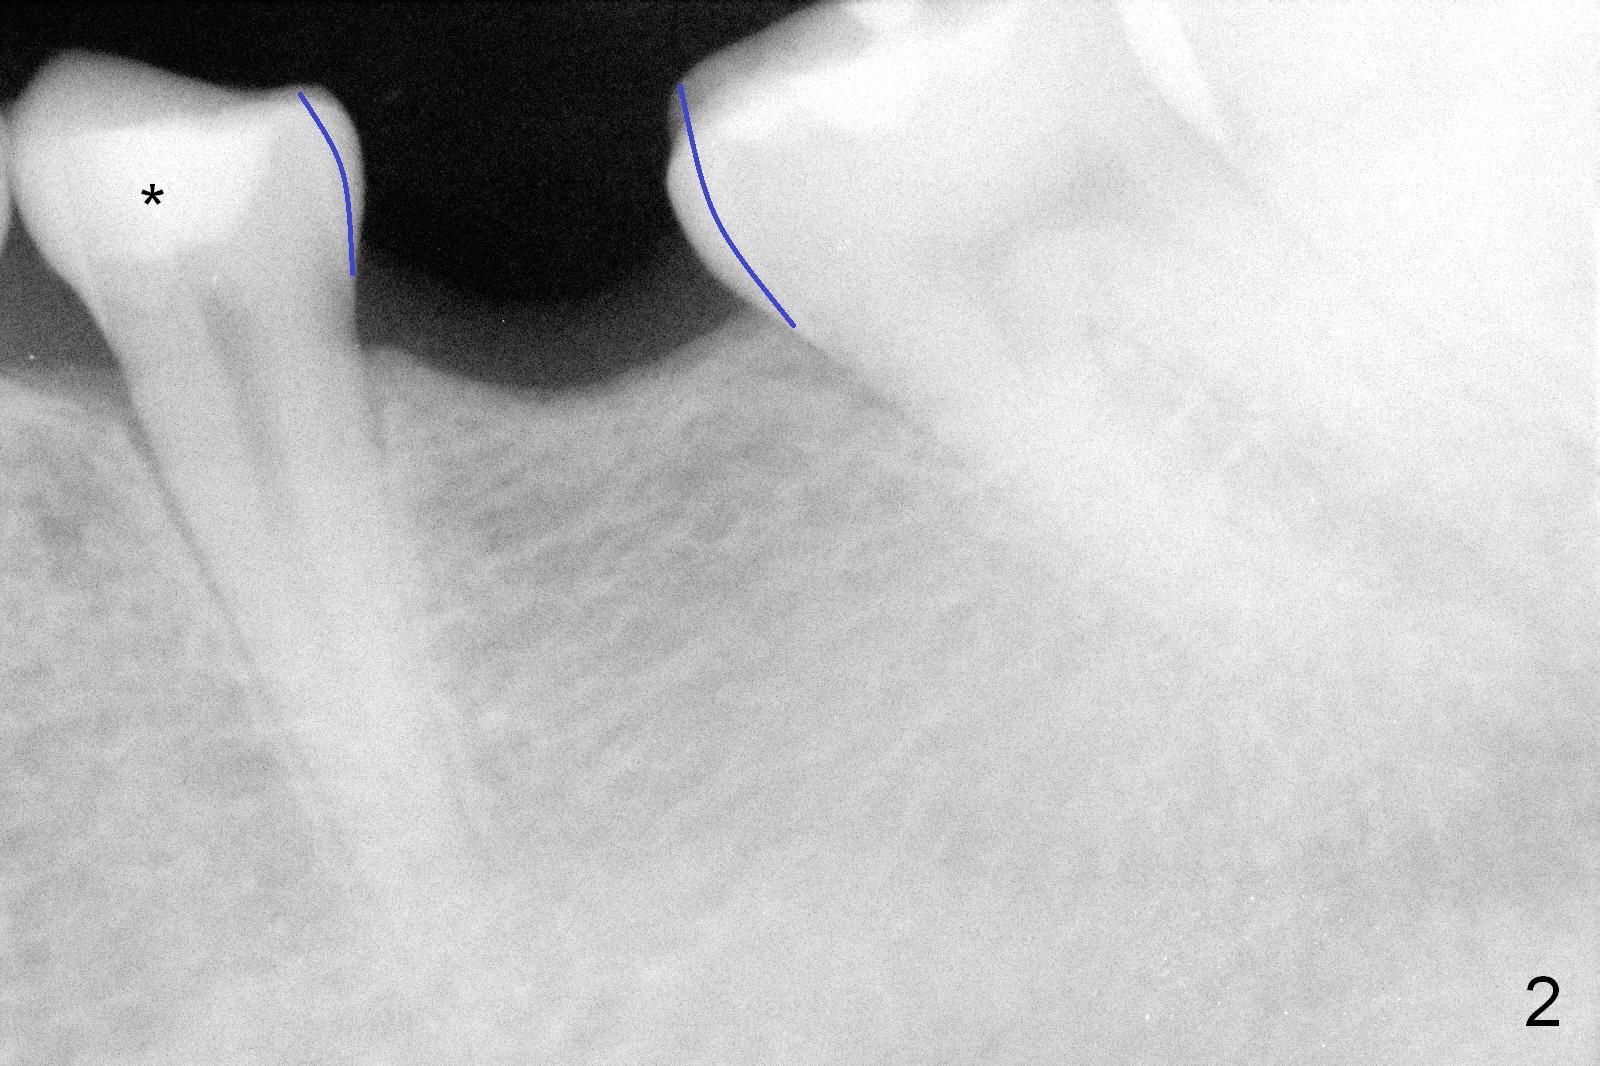

A 31-year-old woman agrees to have implant at #19 (Fig.1) after redoing MOL composite at #20 (Fig.2 *). The edentulous mesiodistal space is narrow (~ 6 mm in Fig.3). If the buccolingual bone width is found to be good after incision, a large implant is preferred. To gain space mesiodistally, the proximal surfaces of the neighboring teeth will be reduced (Fig.2 blue curved lines).